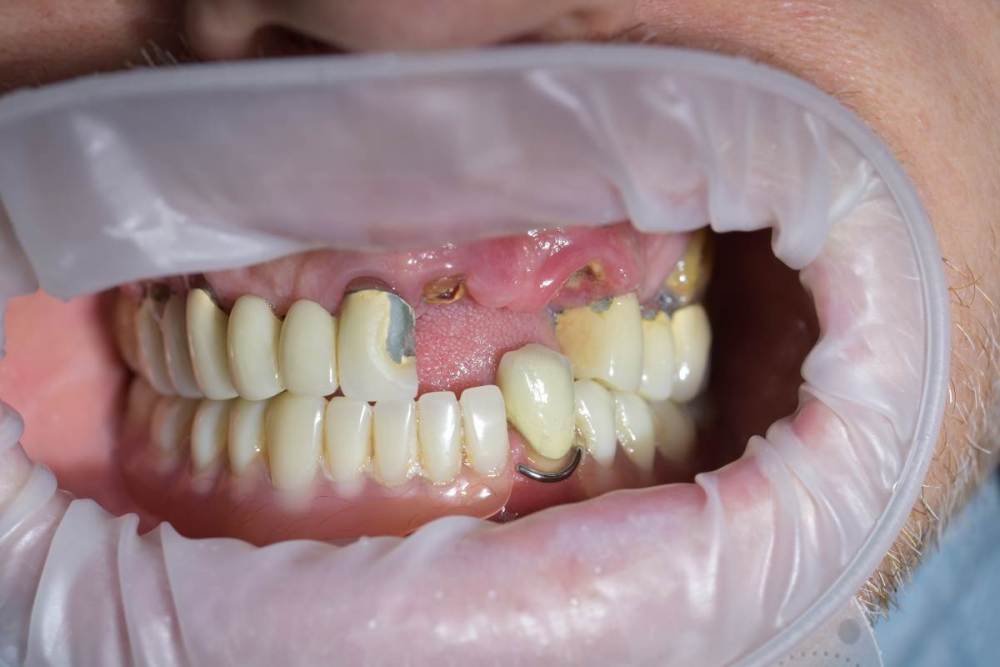

TIGER Опубликовано 13 июня, 2022 Поделиться Опубликовано 13 июня, 2022 (изменено) Всем привет!Довольно сложная исходная ситуация,пожелания пациента минимум вмешательств ,никаких костных пластик.В таких случаях я предпочитаю съёмные конструкции на балочной фиксации из-за возможности гигиены,ибо у так пациентов всё печально с этим.После обсуждения с пациентом он одобрил план действий и будущую конструкцию .Произведено изготовление шаблона,по навигации установлены импланты 4 верх и 4 низ,временные несъёмные конструкции на мультиюнитах,через полгода 2 протеза на балочной фиксации? Изменено 13 июня, 2022 пользователем TIGER 6 1 Ссылка на комментарий

TIGER Опубликовано 13 июня, 2022 Автор Поделиться Опубликовано 13 июня, 2022 Ситуация до Ссылка на комментарий